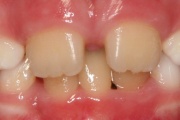

Lutipudelikaariese kahjustused

Lutipudelikaaries